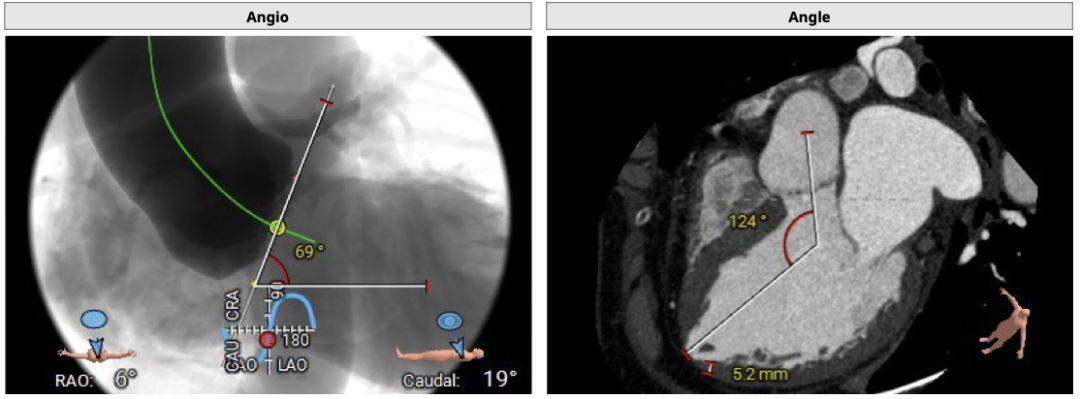

横位心,心室角度69度: